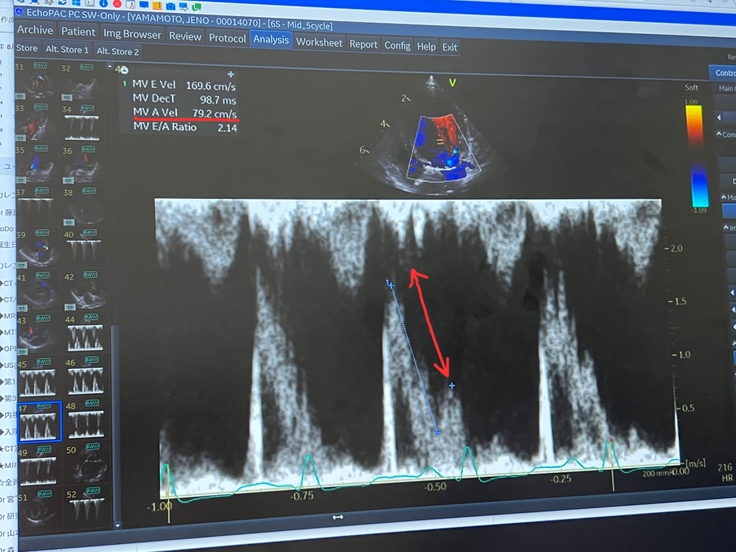

↑赤い矢印の差が大きければ大きいほど、肺水腫になる可能性が高いとの事。ジェノはその差が大きいそうです。